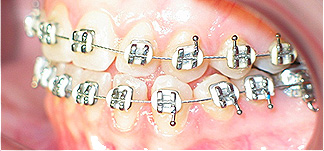

Apinhamento dentário com os dentes caninos em desoclusão (classe II, divisão 2).

Após dois anos de tratamento ortodôntico.